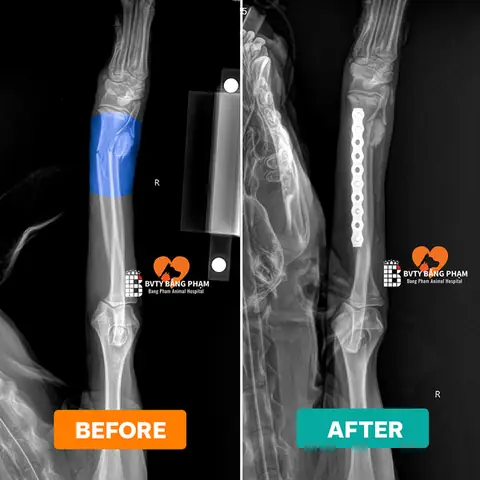

• Chụp X-quang (X-ray): Đây là phương pháp chẩn đoán hình ảnh chính yếu và bắt buộc để xác định chính xác vị trí, loại gãy xương (ví dụ: gãy kín, gãy hở, gãy xương vụn), mức độ nghiêm trọng và số lượng xương bị gãy. Đôi khi, có thể cần chụp nhiều góc độ khác nhau hoặc chụp chân đối diện để so sánh.

• Phẫu thuật chỉnh hình xương (Orthopedic Surgery): Đây là phương pháp điều trị phổ biến và hiệu quả nhất cho hầu hết các ca gãy xương nghiêm trọng. Phẫu thuật đòi hỏi trang thiết bị chuyên biệt và bác sĩ chuyên khoa Ngoại khoa/Chỉnh hình có kinh nghiệm.

• Cố định bên trong (Internal Fixation): Bác sĩ sẽ sử dụng các dụng cụ y tế như nẹp kim loại (bone plates), vít (screws), đinh (pins) hoặc dây (wires) để cố định các mảnh xương gãy lại với nhau từ bên trong cơ thể. Các dụng cụ này thường được để lại vĩnh viễn hoặc gỡ bỏ sau khi xương đã lành hoàn toàn.